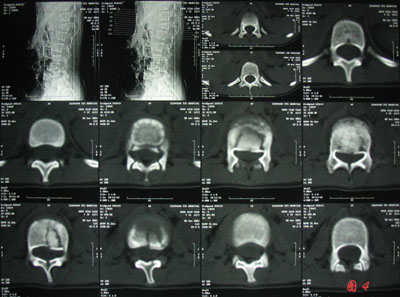

患者:孟某,因坠落伤致全身多发伤,腰1椎体爆裂性骨折脊髓损伤并不全瘫痪,左胫腓骨远端骨折,因患儿年龄小,骨骼正在发育,腰椎椎弓根最宽处不过5mm,手术固定风险较大,内固定材料选择困难。患儿若采用手术复位,椎弓根钉固定,手术时间长、风险大、费用高。稍有不慎就可损伤脊髓致病人瘫痪加重或死亡。但为扩大椎管,为脊髓损伤恢复创造条件,骨二科郭永良主任认真分析了该患者的病情后,决定采用经后路切开复位RSS椎弓根钉固定手术。经过2小时的精心手术,手术取得圆满成功。患者脊髓损伤恢复好,活动自如,生活不受限,已拆除内固定物。(附:图3,图4,图5)